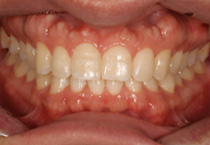

Anterior Crossbite

Case 1

Smile Line case 1 2022.10.06

2022.10.06

Smile Line case 1 2023.02.07

2023.02.07